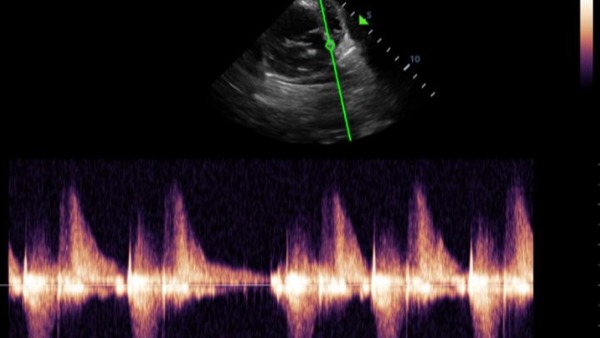

Hola, mi cachorro Pakito sufre de una mal formación en el corazón, tiene displasia en la válvula tricúspide. Explicándolo mal resumido sus válvulas no funcionan adecuadamente y no expulsa la sangre del corazón como debería por lo que el corazón agranda y agranda hasta que colapsa.